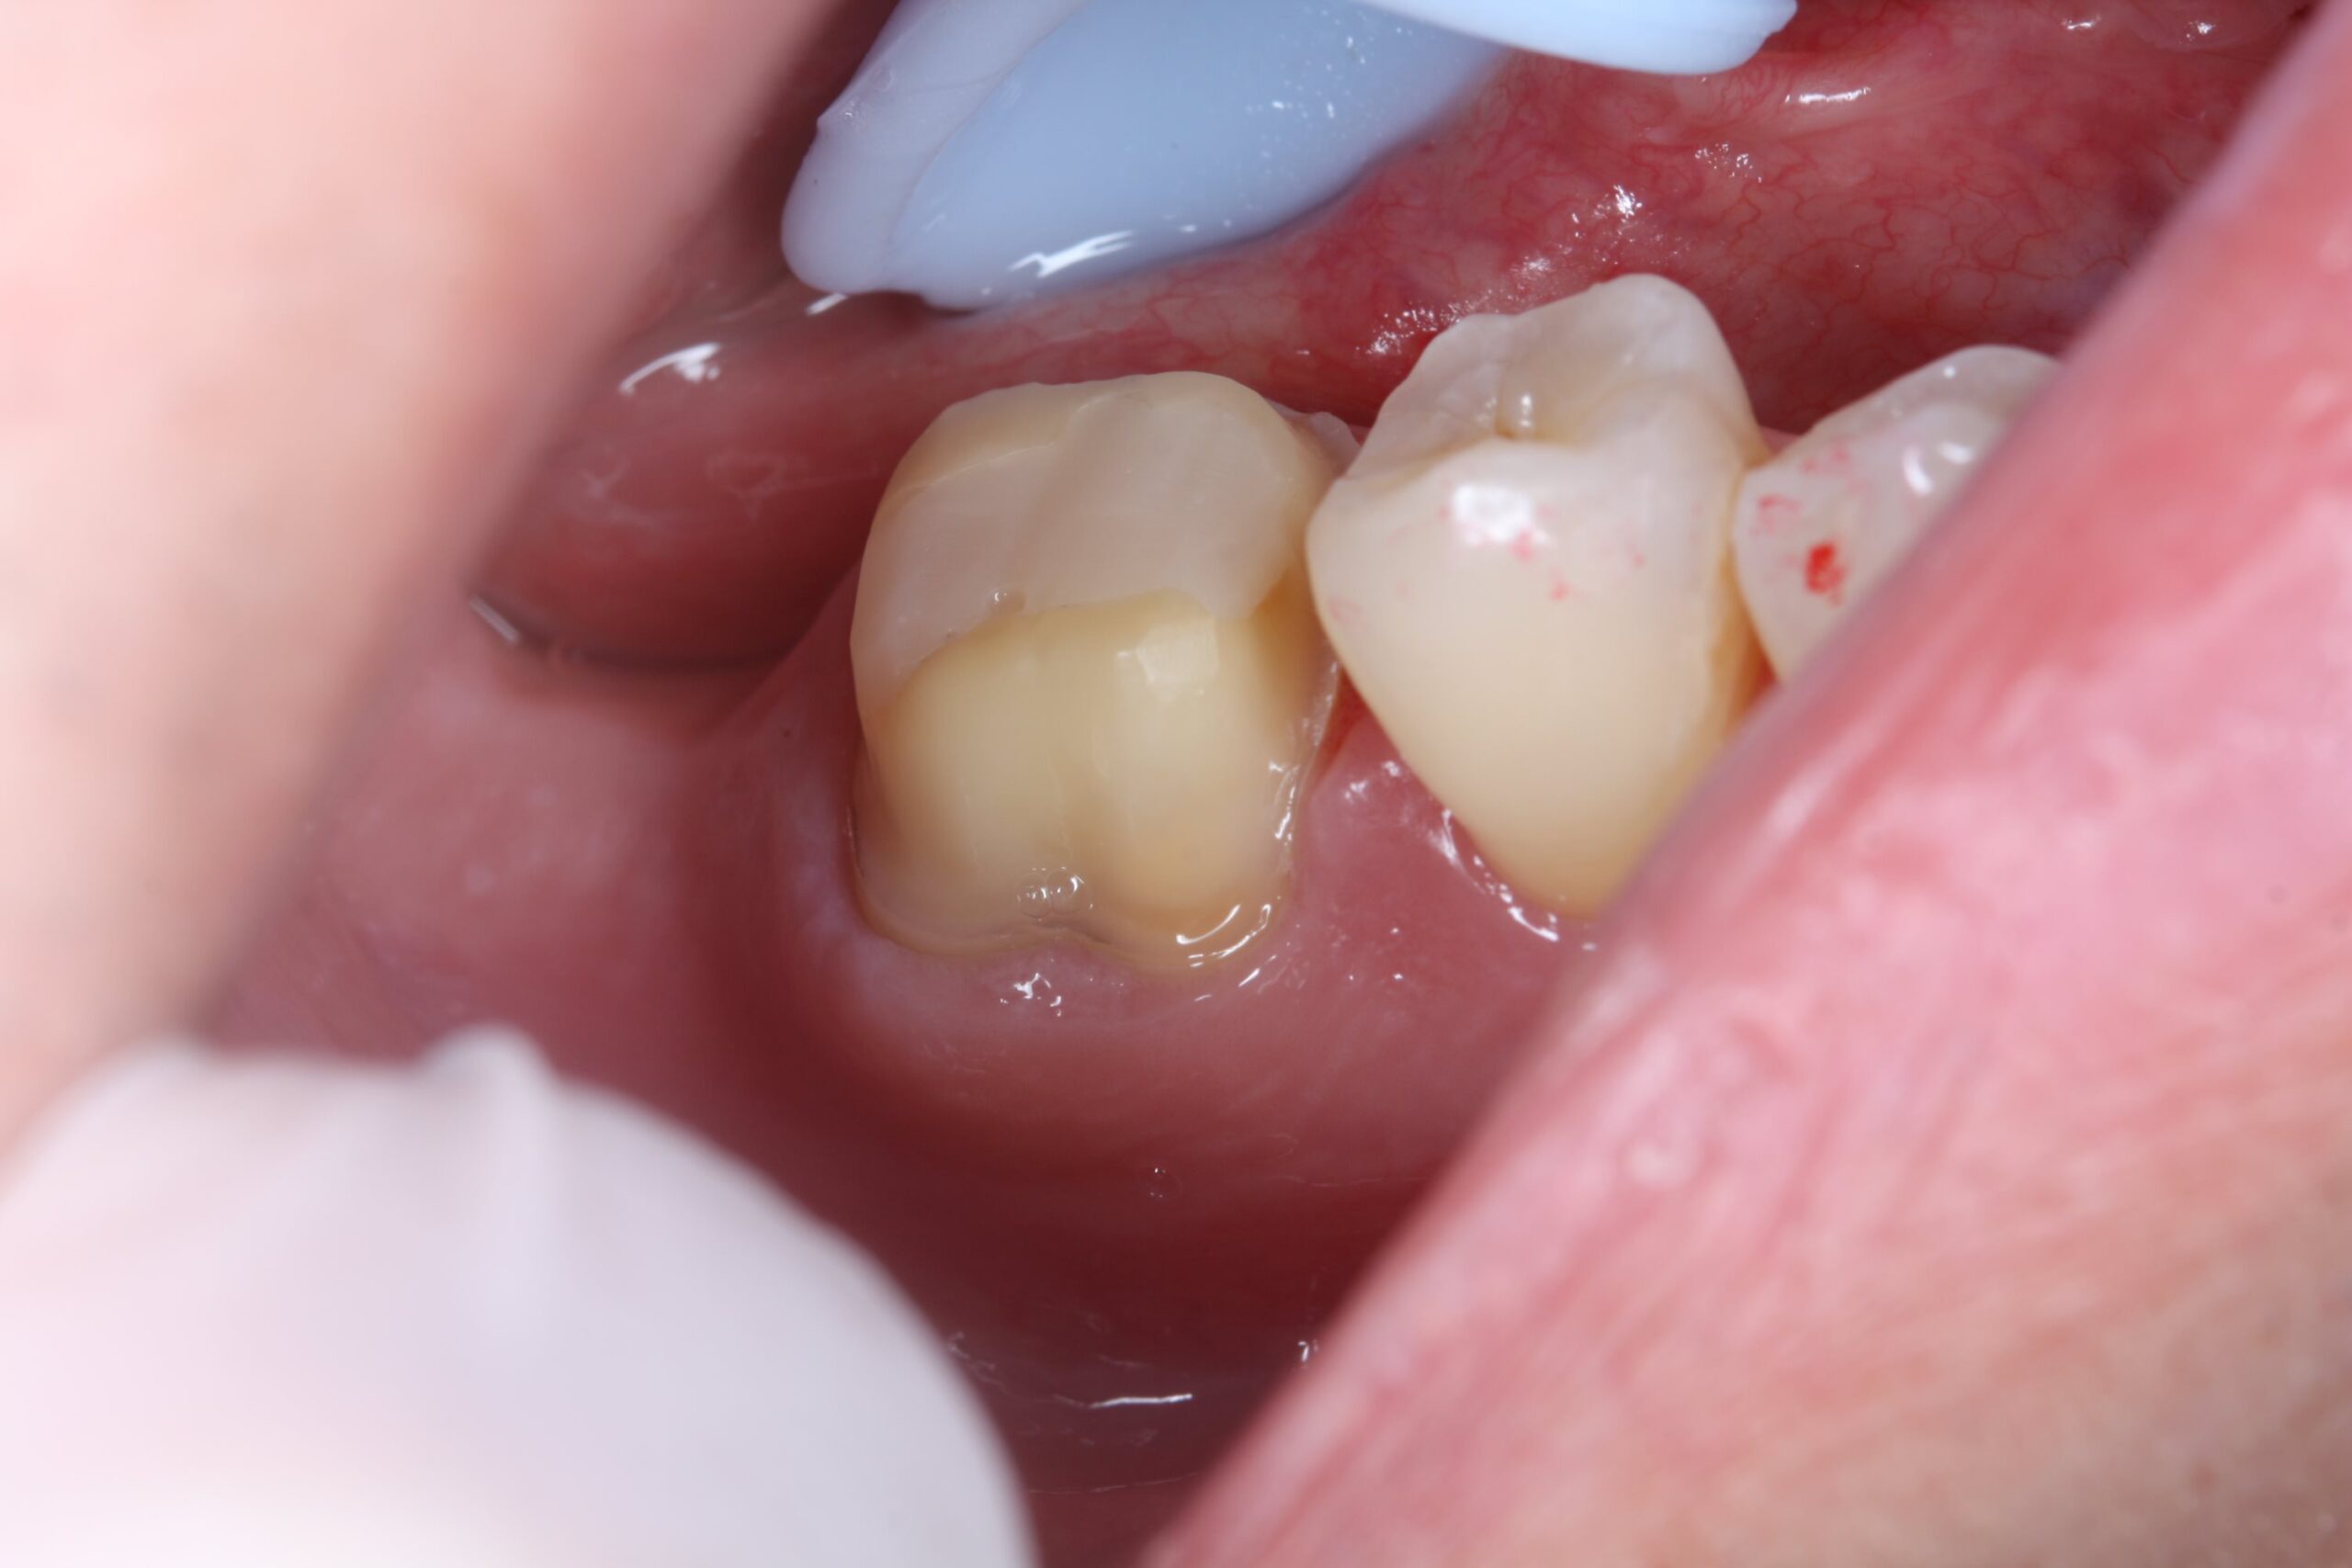

装着前

被せ物が適合しやすいように歯の形を整え、型取りを行いました。

装着前には、接着の妨げになる汚れや唾液をできるだけ取り除き、清潔な状態で処置を行います。 -